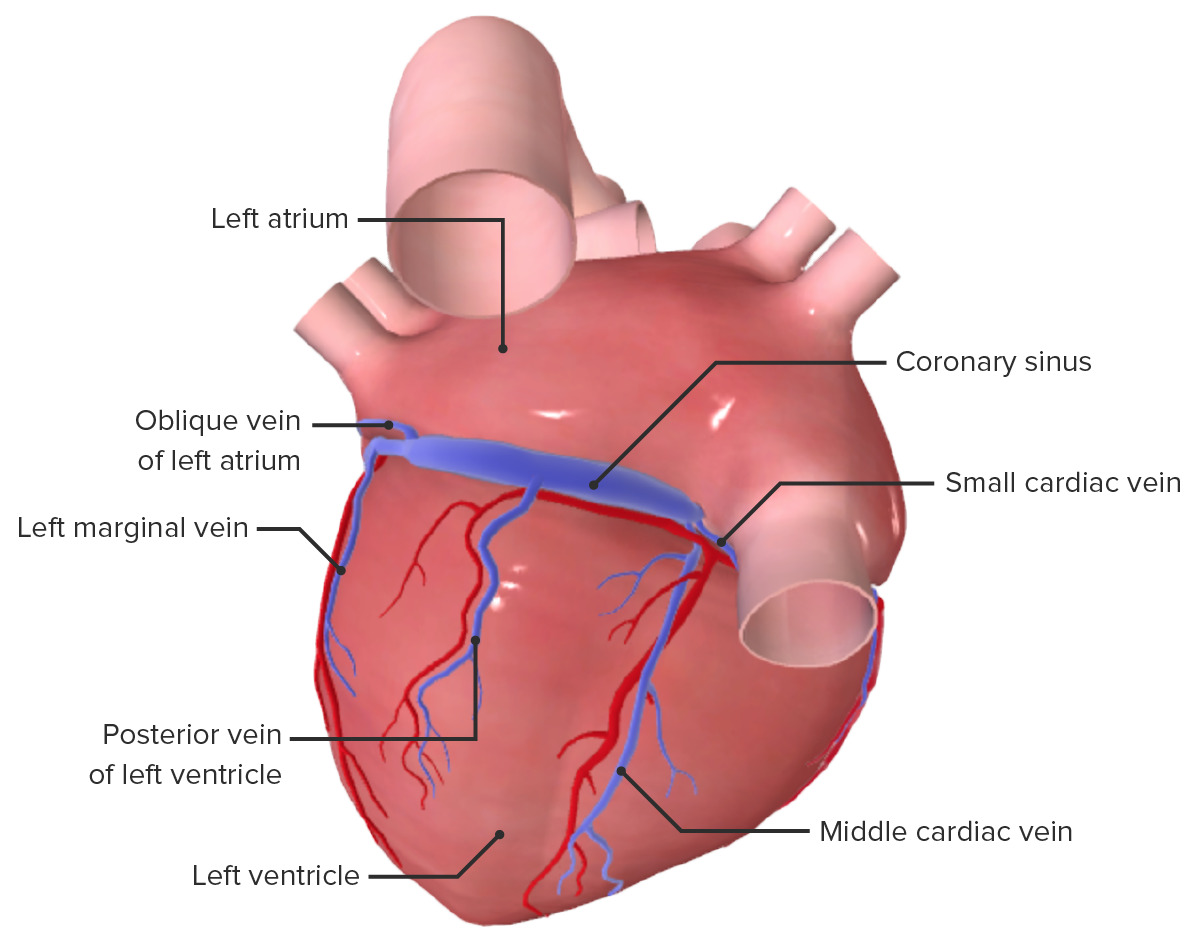

Анатомия желудка и сердца: визуализация и изучение

Раздел: Фотопанорама